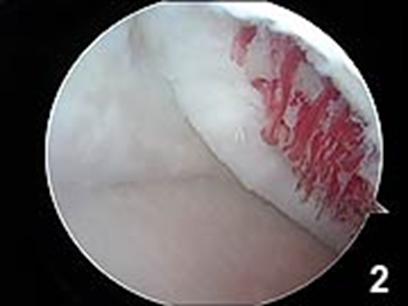

Chirurgul trebuie sa fie foarte atent atunci cand examineaza posteriorul condililor femurali. Daca se semnaleaza orice vatamare/rana/deteriorare pe suprafetele articulare, trebuie sa se cerceteze atent calitatea cartilagiului. Orice flapsuri instabile sunt inlaturate prin folosirea unui aparat de ras electric artroscopic sau curette. Apoi, un curette este folosit pentru a debrida stratul de cartilagiu calcifiat de la baza in toata grosimea defectului. Acest pas se bazeaza pe activitatea lui Frisbi, care a demonstrat vindecarea suprafetei articulare superioare la un cal, cand stratul cartilagiului calcifiat este indepartat. Cand indepartam stratul cartilagiului calcifiat, in general nu se foloseste un aparat de ras. Cu un aparat de ras este dificil de controlat cantitatea de os eliminat, si este posibil ca osul subcondral sa fie afectat.

Dupa indepartarea cu succes a stratului de cartilaj calcifiat, o andrea este folosita pentru a face mai multe gauri mici (mirofracturi) in osul expus al defectului condral aflate la distanta de 1-2 mm. Trebuie lasata o punte de oase potrivita intre gauri. Tehnica de microfracturi are numeroase avantaje fata de foraj. Mai intai de toate, creaza o leziune termala mai mica. Mai mult, cu microfracturi, chirurgul este capabil sa intre in zonele dificile ale suprafetei articulare cu un control mai bun asupra adancimii de patrundere. La finalizarea microfracturii, o suprafata aspra este generata pentru a aderenta cheagului de sange care contine celule mezenchimale nediferentiate de la osul subcondral. Trebuie avut grija ca cele mai marginase parti ale leziuni sa fie patrunse de andrea pentru a ajuta la vindecarea tesutului reparator la imprejmuirea suprafetei articulare. Odata ce microfractura este finalizata, pompa artroscopica este oprita pentru a se asigura ca sangerarea maduvei curge din gaurile mici umpland defectul.[54]

Artroscopia arata repararea tesuturilor la sase saptamani.